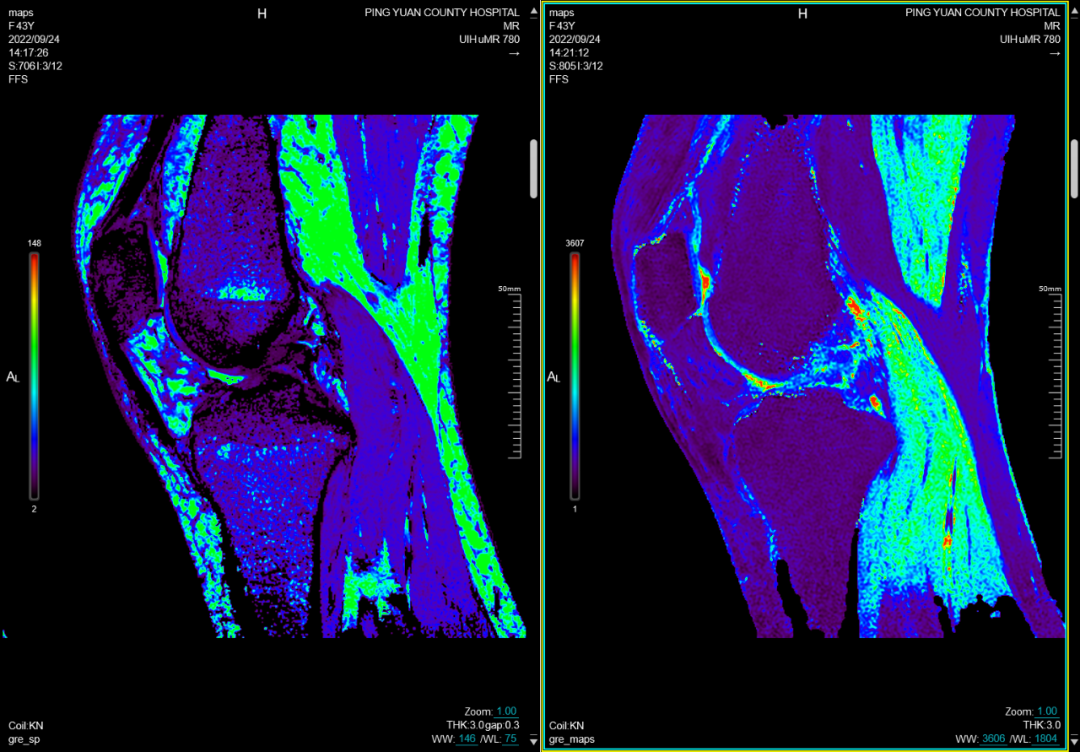

六、在四肢及关节检查方面:图像更清晰,后处理功能更丰富

MRI彻底变革了骨骼肌肉结构的成像,主要应用于创伤、关节炎、肿瘤和感染等方面。在创伤方面可显示平片或CT不能显示的病变如骨挫伤或骨小梁骨折,隐匿性骨折平片甚至CT易漏诊,而MRI能清晰显示。MRI是无创评估关节内软骨的最佳检查手段,能清晰观察软骨细微变化。

(膝关节MR检查及后处理)